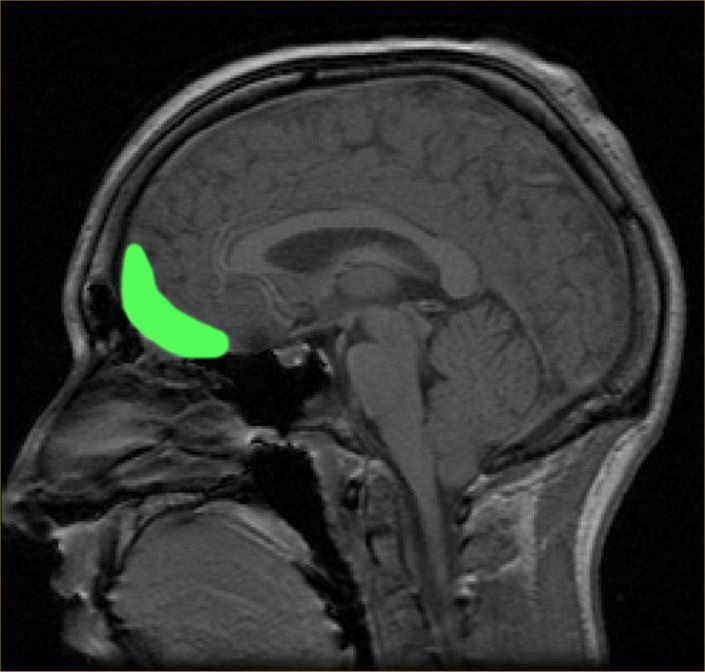

The brains of 909 people in China were scanned with an MRI. Half had depression and half didn't (421 to 488). The medial and lateral orbitofrontal cortexes (OFC) responsible for emotion and rewards/punishment operated differently in those who had depression. The lateral OFC activates when we are disappointed, like when an expectation is not met. For people with depression, this area of the brain was more connected to the area for our sense of self and identity, the precuneus.

A number of studies have demonstrated that activation of the amygdala with concomitant emotional arousal is very quickly followed by activation of the OFC and – in healthy individuals – suppression of the amygdala response. This suppressive function of the vmPFC/OFC is supported by a large body of preclinical data. It is likely that this function is impaired in depression, with the suppressive/repressive action of the vmPFC/OFC being dominated by persistent flurries of limbic arousal.